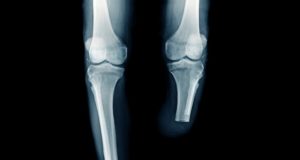

Changing the game in knee osteoarthritis: A vascular approach

Chinmaya Shelgikar, MD, discusses the benefits of vascular surgeons performing geniculate artery embolization.

Geniculate artery embolization (GAE) is an intra-arterial, catheter-based procedure used to treat chronic...